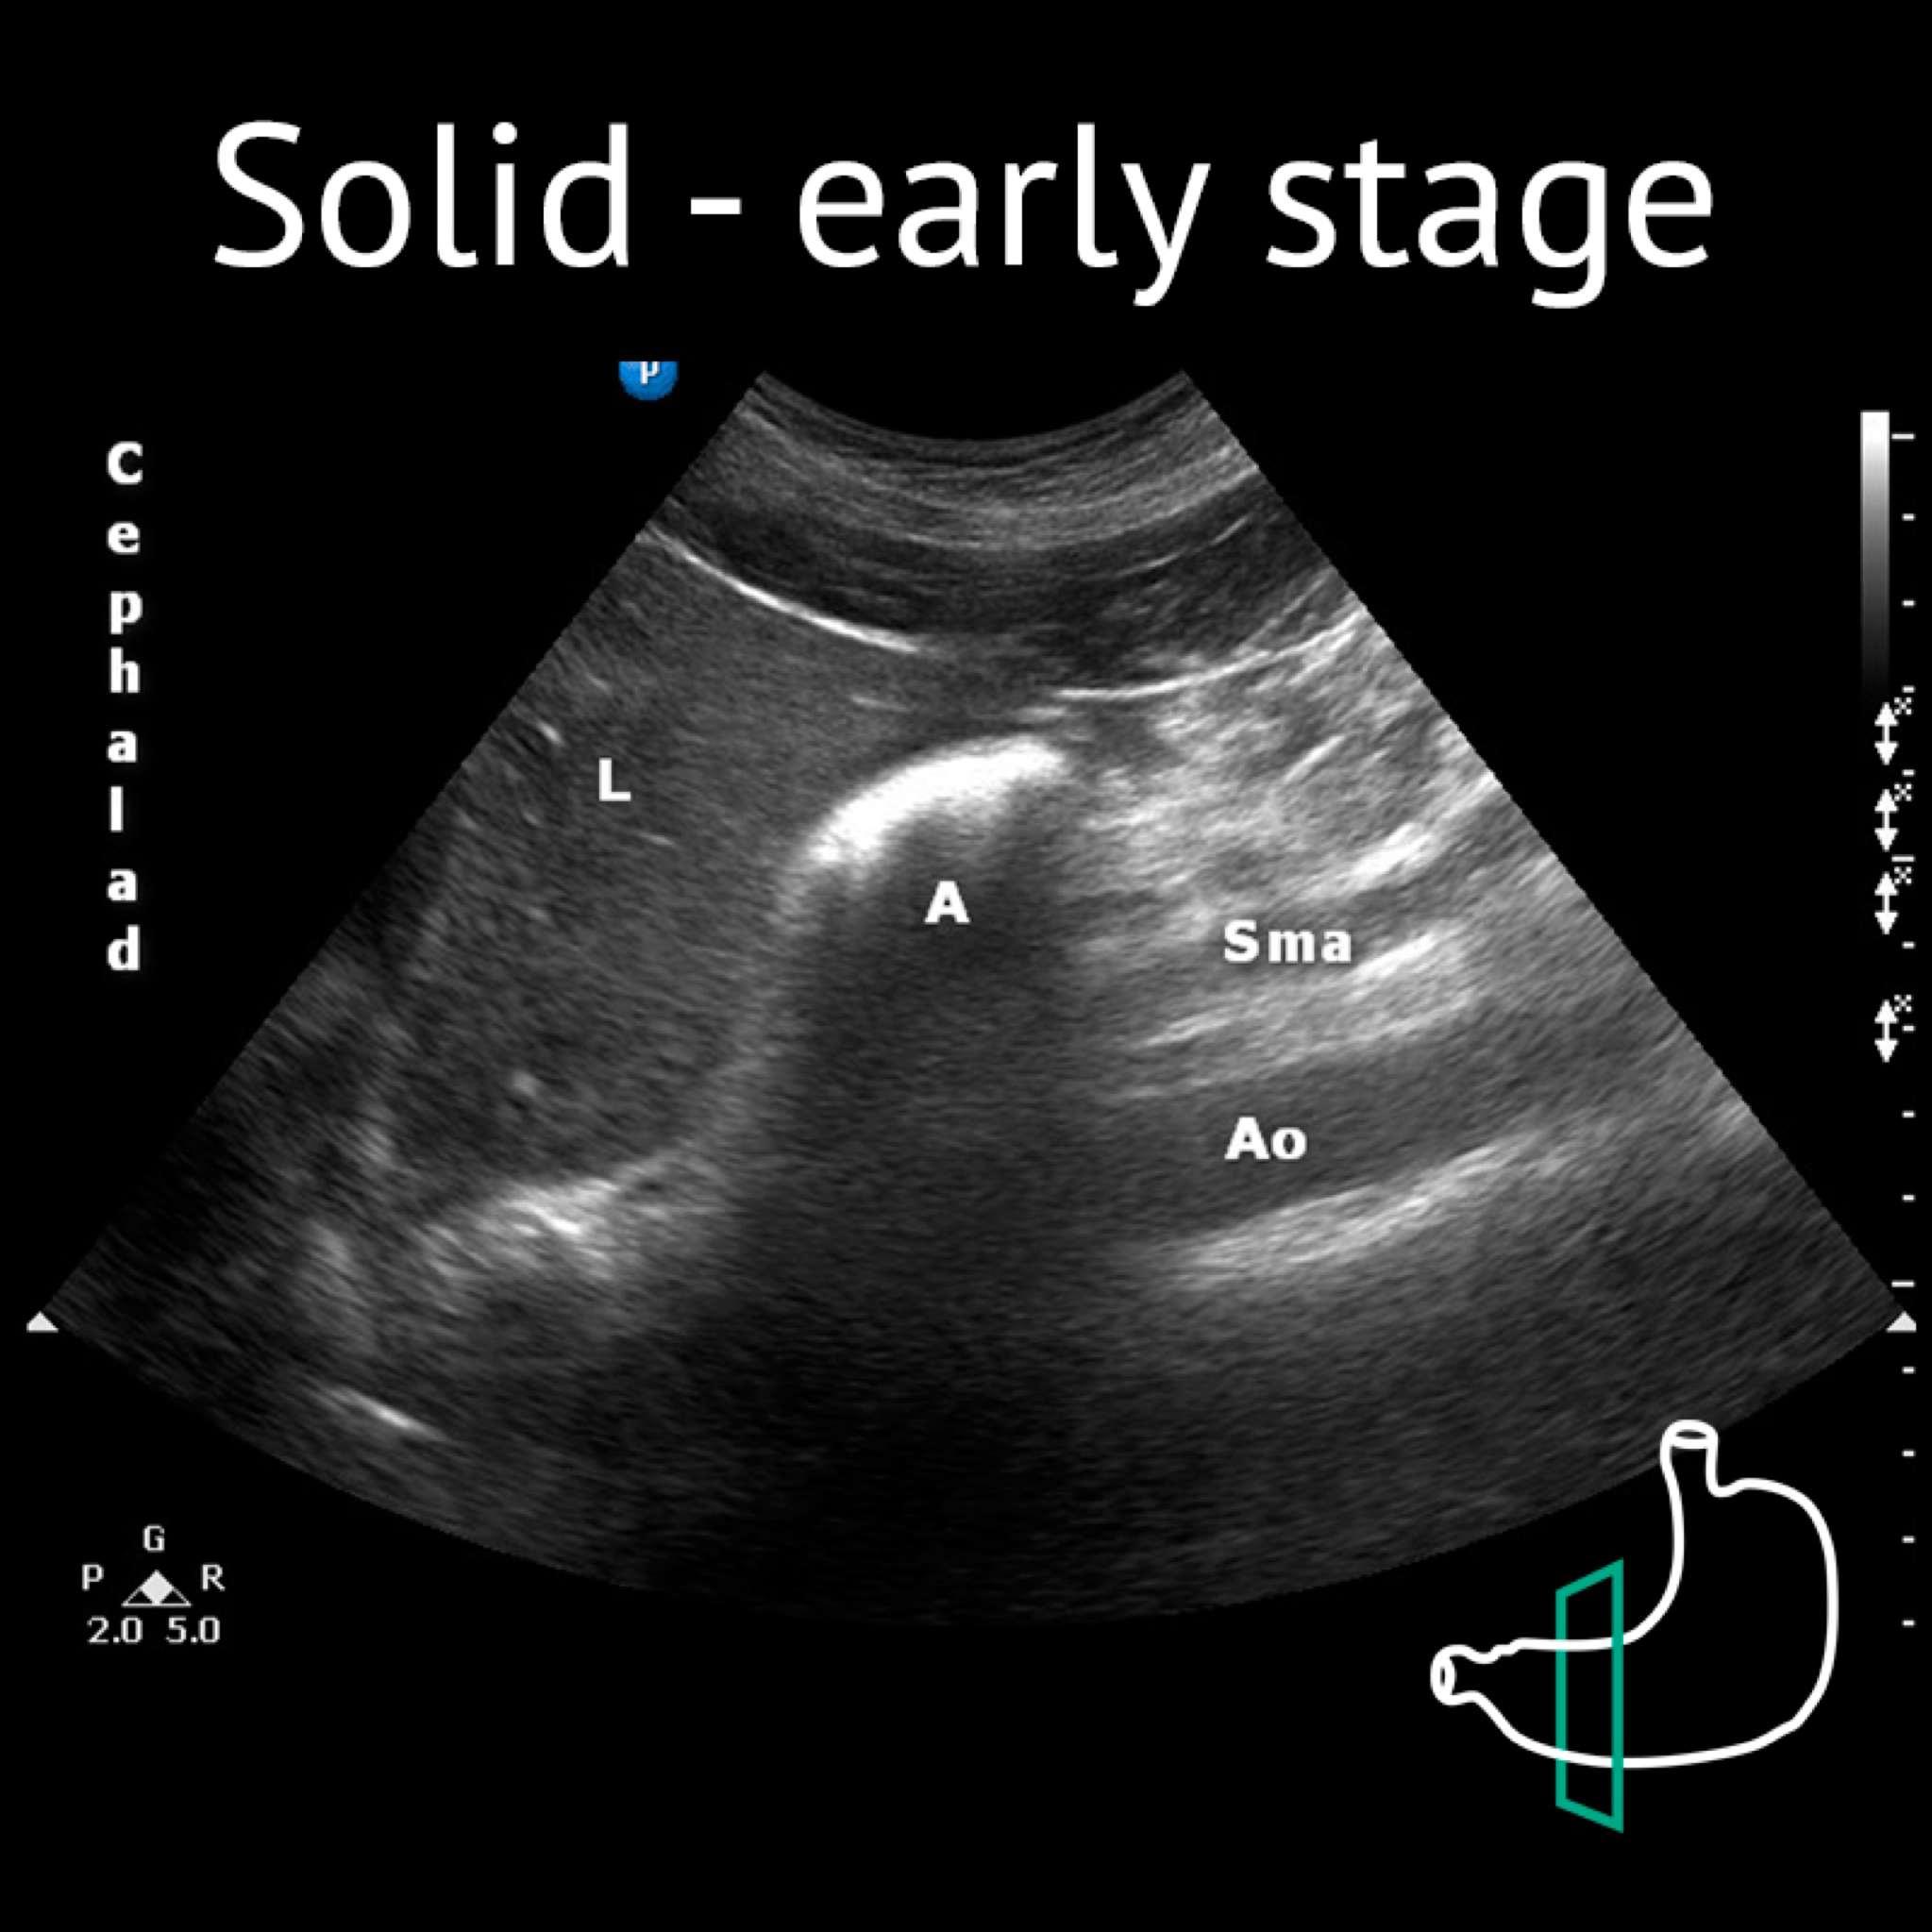

A: antrum; Ao: aorta; L: liver; P: pancreas; Sma: superior mesenteric artery